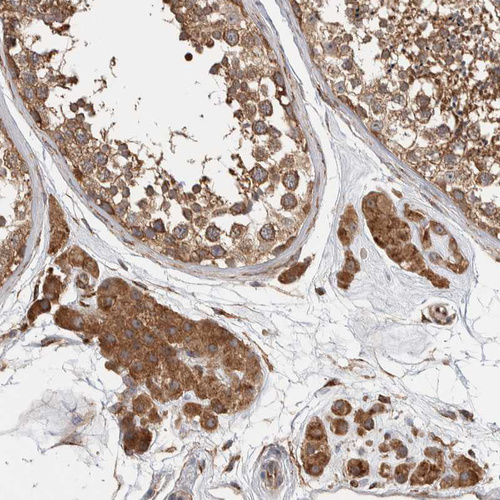

Immunohistochemical staining of human duodenum shows strong cytoplasmic positivity in lymphoid cells.